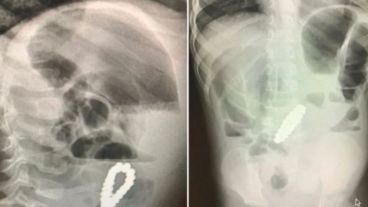

Al examinar al niño, los médicos le diagnosticaron apendicitis aguda pero después de someterse a una apendicectomía para extirpar el apéndice su dolor de estómago continuó. Cinco días después del procedimiento, los médicos realizaron una ecografía y descubrieron un brazalete dentro del estómago.

El pequeño tuvo una laparotomía urgente para extraer el objeto, que resultó ser un brazalete compuesto por 18 cuentas magnéticas de forma hexagonal.

La pulsera había estado obstruyendo sus intestinos y cavando cuatro pequeños agujeros en ellos, que los médicos pudieron reparar.